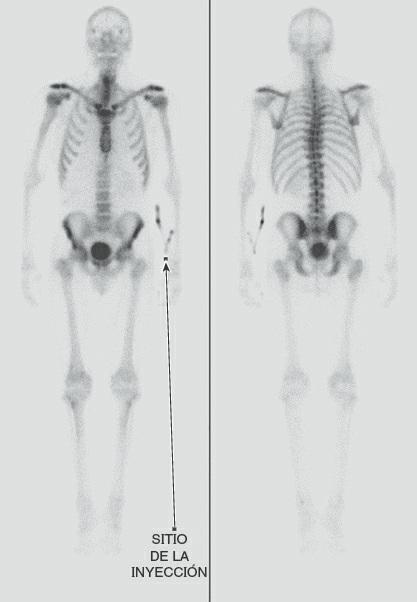

Las técnicas de gammagrafía proporcionan información sobre la distribución o la concentración de cantidades mínimas de sustancias radiactivas introducidas en el organismo. Las imágenes gammagráficas muestran los órganos después de la inyección intravenosa de una pequeña dosis de un isótopo radiactivo. La sustancia se utiliza para marcar un compuesto que es captado selectivamente por el órgano a estudiar, como el difosfonato de metileno con tecnecio 99m (99mTc-MDP) para la gammagrafía ósea (fig. 1-56).

En la tomografía por emisión de positrones (PET, positron emission tomography) se utilizan isótopos producidos por un ciclotrón, con una semivida extremadamente corta, que emiten positrones. La PET se usa para valorar las funciones fisiológicas de órganos como el cerebro, sobre una base dinámica. Las áreas de actividad cerebral aumentada mostrarán una actividad selectiva del isótopo inyectado. Pueden visualizarse las imágenes de todo el órgano o de cortes transversales. Las imágenes obtenidas mediante tomografía computarizada con emisión de fotón único (SPECT, single photon emission computed tomography) son similares, pero el marcador empleado tiene una mayor duración. La técnica es menos costosa, pero requiere más tiempo y su resolución es menor.